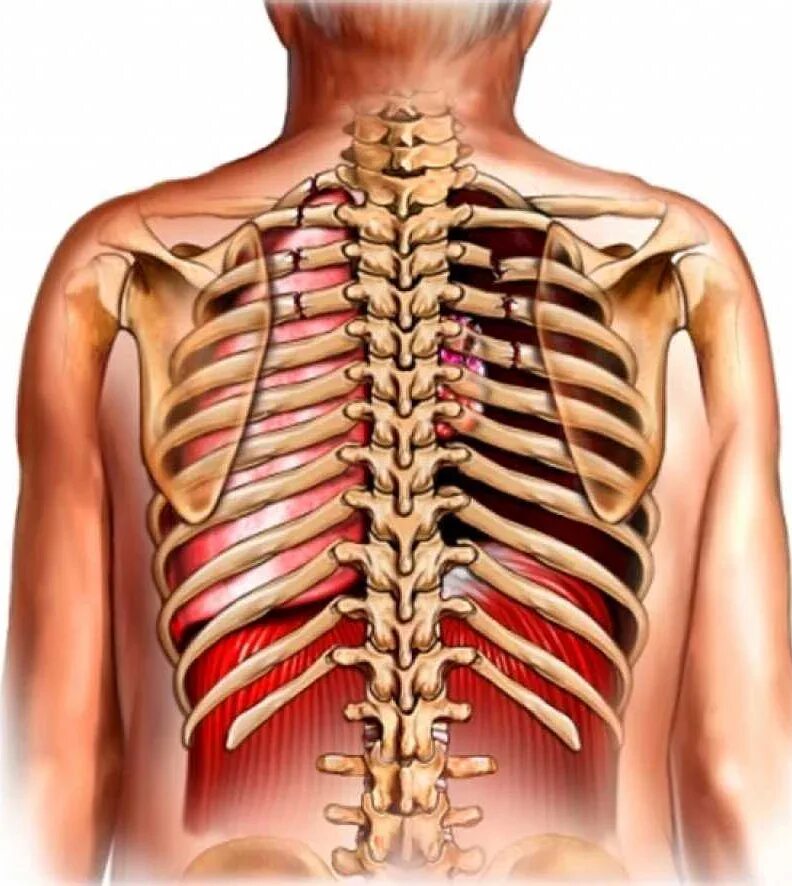

Как определить перелом ребра или ушиб